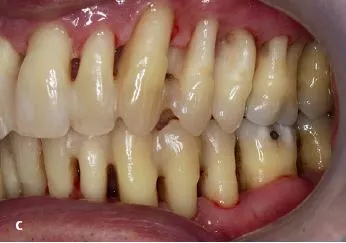

Ein Jahr nach Abschluss der aktiven Phase zeichnet sich eine positive Entwicklung ab. Die Sondierungstiefen sind deutlich reduziert (< 7 mm); deutliche Verbesserungen wurden bezüglich der Blutung (BOP 35%) und der Belagsbildung (QH 27%) registriert (Abb. 2a–c).

Auffällig ist die Verringerung der Überempfindlichkeiten, die bereits nach kurzer häuslicher Anwendung von Enamelon® Gel trotz der geringen Fluoridkonzentration eintrat. Die Reduktion der Überempfindlichkeiten war derart substanziell, dass bereits bei der ersten UPT ohne begleitende Anästhesie maschinell subgingival gearbeitet werden konnte. Der Effekt ist allerdings ? wie bei allen oberflächlich und somit auch allen vom Patienten applizierten Medikationen – nur von temporärer Wirkung [4]. Bei Verzicht auf die Anwendung von Enamelon® war daher ein zeitnaher Wiederanstieg der Überempfindlichkeiten zu verzeichnen. Für den Patienten ist ein Zusammenhang zwischen der Reduktion der Überempfindlichkeiten seiner Zähne und der Anwendung des Produktes ersichtlich; daher wendet er das Gel regelmäßig an.